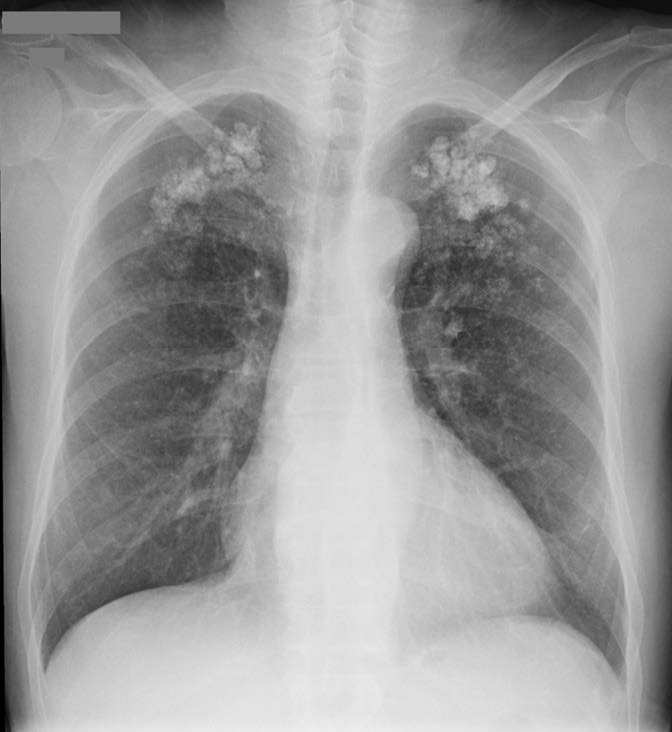

Figure 1: Chest radiograph showing numerous small nodular opacities with patchy areas of parenchymal opacification in both upper lung zone.

A 57-year-old man with long-lasting chronic kidney disease due to post-streptococcal glomerulonephritis was referred to our nephrology clinic to perform a second renal transplantation. The patient had a 28-year history of hemodialysis treatment and a first kidney transplant failure. Impaired renal function with normal calcemia, slightly elevated phosphorus, and hyperparathyroidism were observed through laboratory tests. During the previous 3 months, he had a history of non-productive cough with persisting dyspnea. His physical examination was unremarkable. The chest radiograph (Fig.1) revealed numerous small nodular opacities with patchy areas of parenchymal opacification. The nodules were predominant in the upper lung zone and calcification of the nodules was evident. Computed tomography (CT) of the chest showed multiple ground-glass opacities associated with poorly defined centrilobular nodules with ground-glass attenuation and coarse areas of calcification (Fig. 2). There was a symmetrical distribution involving both upper lung lobes and also bronchial calcifications (Fig. 3). There were no visible signs of pleural effusion, pulmonary fibrosis, or lymphadenopathy. Based on these findings and in this setting of end-stage renal disease, the diagnosis of metastatic pulmonary calcification (MPC) was made. Attempt to normalize the patient’s calcium and phosphate biochemistry has been the mainstay of therapy. Following treatment, the patient’s imaging abnormalities have been stable, and he is now waiting for a new transplant match.